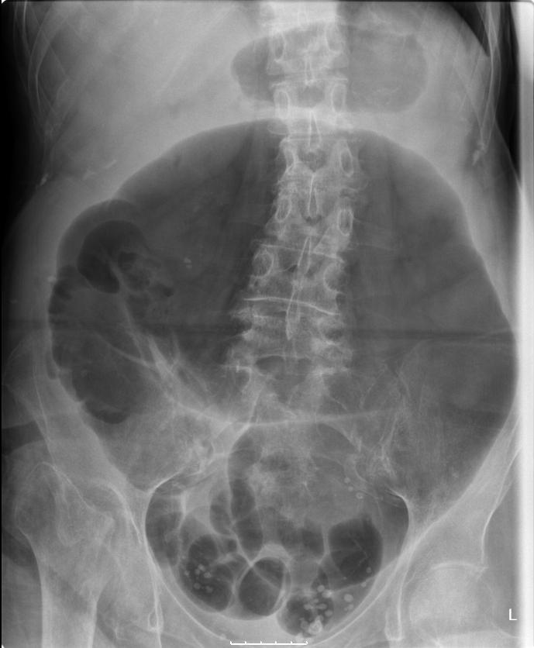

pt w/ volvulus

what is this an image of?

volvulus

twisting of bowel on itself

subtracive → decrease techniquue due to abundance of air

what are the technique factors of a patient w/ volvulus?